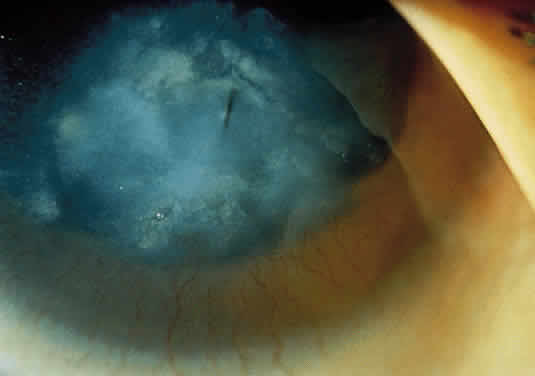

microscopic study. Invest Ophthalmol 12:366, 1973 137. Walton D, Robb R, Crocker A: Ocular manifestations of group A Niemann-Pick